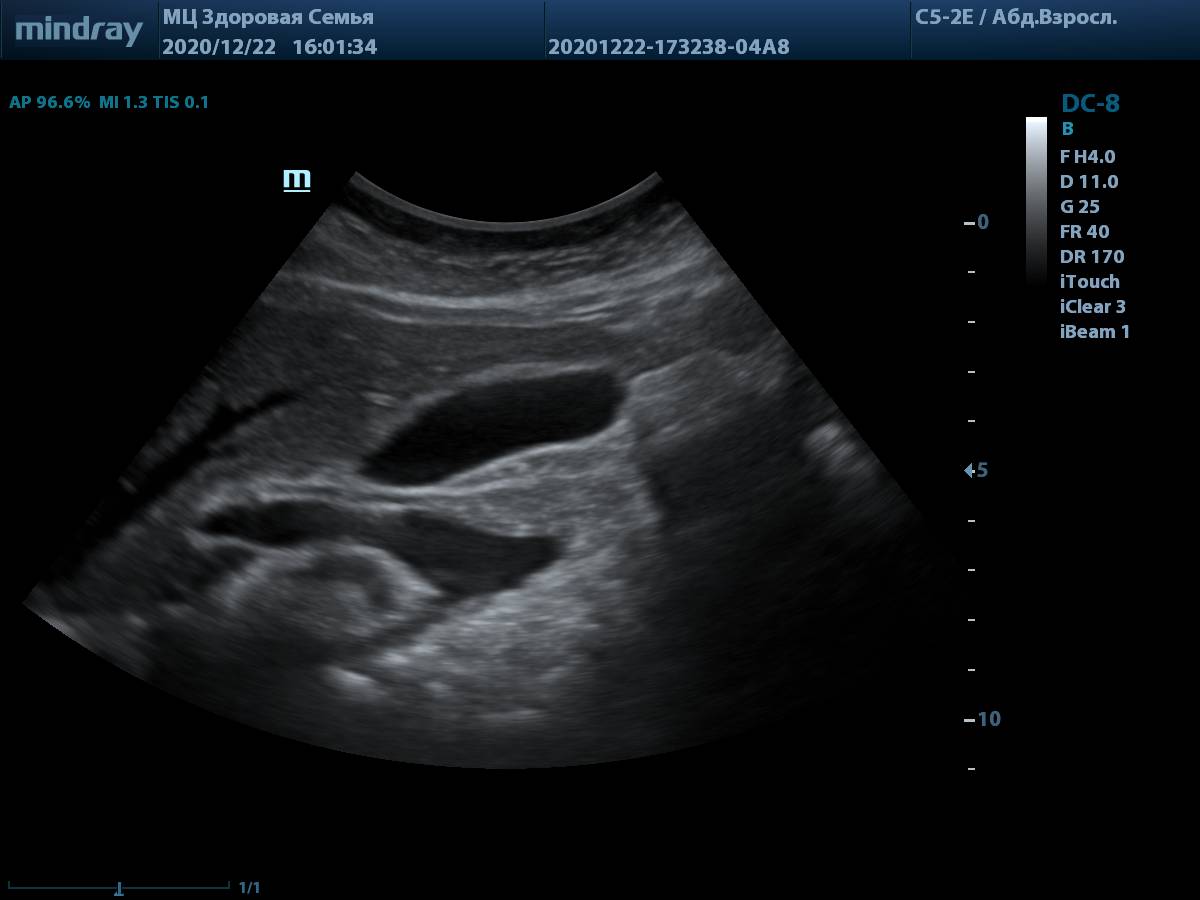

6. Пример визуализации ворот печени у пациента с избыточной массой тела. Четкие контуры холедоха и портальной вены, идеально для проведения измерений.

Визуализации ворот печени